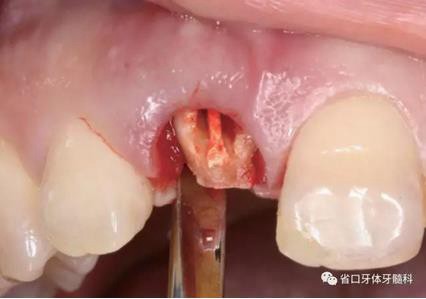

(1)微創(chuàng)拔牙及即刻種植:術(shù)前拍攝口內(nèi)照及實(shí)施牙周基礎(chǔ)治療。常 規(guī)消毒鋪巾阿替卡因局麻下微創(chuàng)拔除上頜右側(cè)中切牙,搔刮拔牙窩及根尖肉 芽組織。探測牙槽骨唇側(cè)骨壁及鄰面牙槽嵴完整,牙齦無撕裂。不翻瓣下于上頜右側(cè)中切牙缺隙近遠(yuǎn)中中點(diǎn)的腭側(cè)牙槽骨及根方定位,按照逐級預(yù)備的原則,緊貼牙槽窩腭側(cè)骨壁制備種植窩洞,植入Zimer®3.7mm×13mm TSV種植體1顆,植入扭矩>35N·cm,以O(shè)sstell測量種植體的ISQ值為68。 種植體平臺(tái)位于唇側(cè)齦緣中點(diǎn)下3mm,與唇側(cè)骨壁內(nèi)側(cè)面形成的跳躍間 隙約2mm,置入Bio-Oss®細(xì)顆粒骨粉0.25g,上愈合基臺(tái)關(guān)閉創(chuàng)口。術(shù)后 CBCT檢查顯示:種植體利用牙槽窩根方骨質(zhì)固位,緊貼牙槽窩腭側(cè)骨壁, 其唇側(cè)面與牙槽窩唇側(cè)骨壁的內(nèi)側(cè)面所形成的跳躍間隙(約2mm)可見顆 粒狀顯影物充填。牙槽窩的唇側(cè)骨壁及唇側(cè)倒凹無缺損穿孔。

圖9 探測唇側(cè)骨壁完整

圖10 唇側(cè)骨壁完整